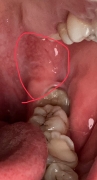

[写真あり] 奥歯の奥の歯茎に痛みがある

写真から親知らずは半埋伏で見えるのですが、ここでは診断は出来ないですし、しかるべき処置をしないと収まらないこともあるので、時間が取れれば早目に歯科医院に行った方がいいと思います。

この辺りは口腔外科の領域なので、口腔外科と書いてある歯科医院がいいでしょうね。